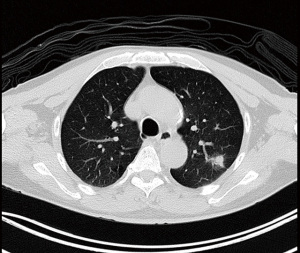

Patient is a 69 years old male non-smoker with a past history of carcinoma of prostate. During routine positron emission tomography (PET) computed tomography (CT) surveillance scan for prostate cancer a solitary left upper lobe spiculated nodule suspicious for lung cancer was detected (Figure 1). He underwent a left VATS wedge excision of the nodule. Intraoperative frozen section analysis of the nodule confirmed it to be a non-small cell lung cancer. A completion left VATS upper lobectomy and systematic lymph node dissection was done at the same session. During the lobectomy the interlobar lingula A4 and A5 vessels were noted to be small. After division of the upper lobe truncus and interlobar arterial branches a mediastinal origin of a segmental artery was noted. Due to the mediastinal origin and the small interlobar A4+5 lingula branches it was deemed to be a mediastinal lingula artery and was stapled and divided. However during mobilisation of the left upper lobe bronchus it was noted that the divided mediastinal artery was actually supplying the anterior (S8) segment of lower lobe and not the lingula segment. The lobectomy was completed by dividing the upper lobe bronchus and major fissure with staplers. Primary anastomosis of the divided A8 vessels was then reconstructed by VATS. The proximal and distal ends were mobilised to ensure a tension free anastomosis. Proximal and distal control of the pulmonary vessels was obtained with vascular clamps. The proximal and distal stapled ends were divided and primary end to end anastomosis was done with two continuous 6-0 prolene sutures, starting first with the posterior vascular wall and then finishing with the anterior wall. After completion of the anastomosis the clamps were removed and the anastomosis was checked for patency and hemostasis. Air leak check was done followed by application of tissue glue (Video 1). Patient made an uneventful recovery and was discharged on post-operative day 2. Final histology was adenocarcinoma stage 1a (T1N0M0). A retrospective review of a CT coronary scan done 6 years previously did demonstrate the presence of this anomalous vessel (Video 2).